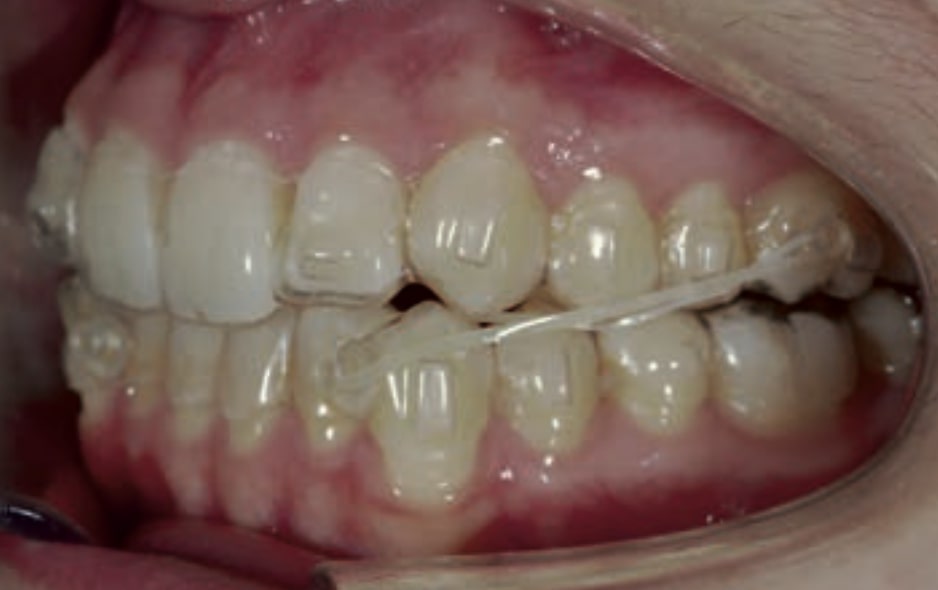

Chief complaint: The patient, a 19-year-old woman, was evaluated to undergo orthodontic treatment using the Angel Aligner Pro system. She presents with a skeletal Class III, mesofacial, with a dental Class III malocclusion and a 2 mm deviation of the lower midline to the left. Teeth 33 and 43 are out of the arch and cortical bone, with a crossbite issue on tooth 33. Fortunately, no functional issues affecting swallowing or breathing have been detected. The patient’s motivation for starting treatment was a general review of her dental and aesthetic health. The soft tissue analysis reveals mandibular protrusion that influences her facial profile. This diagnosis highlights the need for a comprehensive approach to address dental and skeletal misalignments, improving both the patient’s functionality and facial aesthetics.

- Dental Class III, 2 mm deviation of the lower midline to the left. 33 and 43 out of the arch and the cortical bone.

- Crossbite of 33.